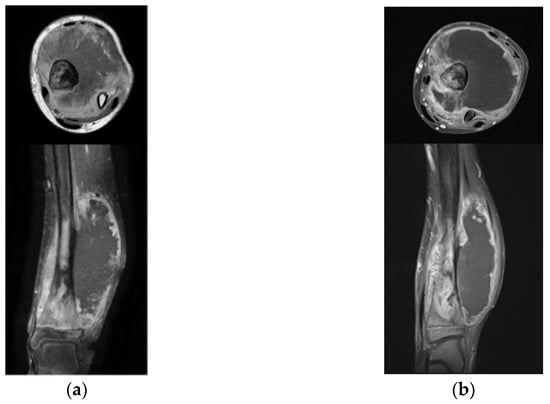

Regarding response during the window therapy, two patients (28.6%) were assessed as good responders and completed the regimen as planned (Figure 2, patient No. 6).

Figure 2.

Representative case 1. The patient (patient No. 6) presented with a lytic lesion and peritoneal reaction at the distal tibia (a). Biopsy revealed conventional osteosarcoma, and the patient underwent CBDCA + IFO chemotherapy. After the window therapy, the tumor shrunk (assessed as good responder); however, due to the progression around the nerve-vessel bundles, amputation below the knee joint was performed (b). After surgery, the patient completed the mOS-91 regimen, and there is currently no evidence of disease. CBDCA, carboplatin; IFO, ifosfamide; mOS-91, modified OS-91.